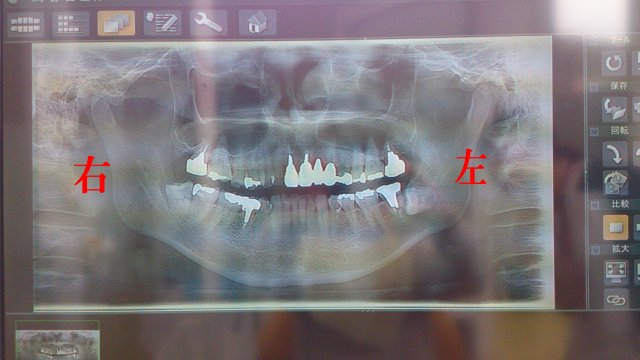

Dsc_28001 わっちの右下の親知らず、根っこが神経と動脈に近いから抜くの難しいらしい。

近所のレントゲンも撮らない歯医者で抜いてたら大変なことになってたぉ。

左下の親知らずは寝てるから放置しててもいいそうだぉ。